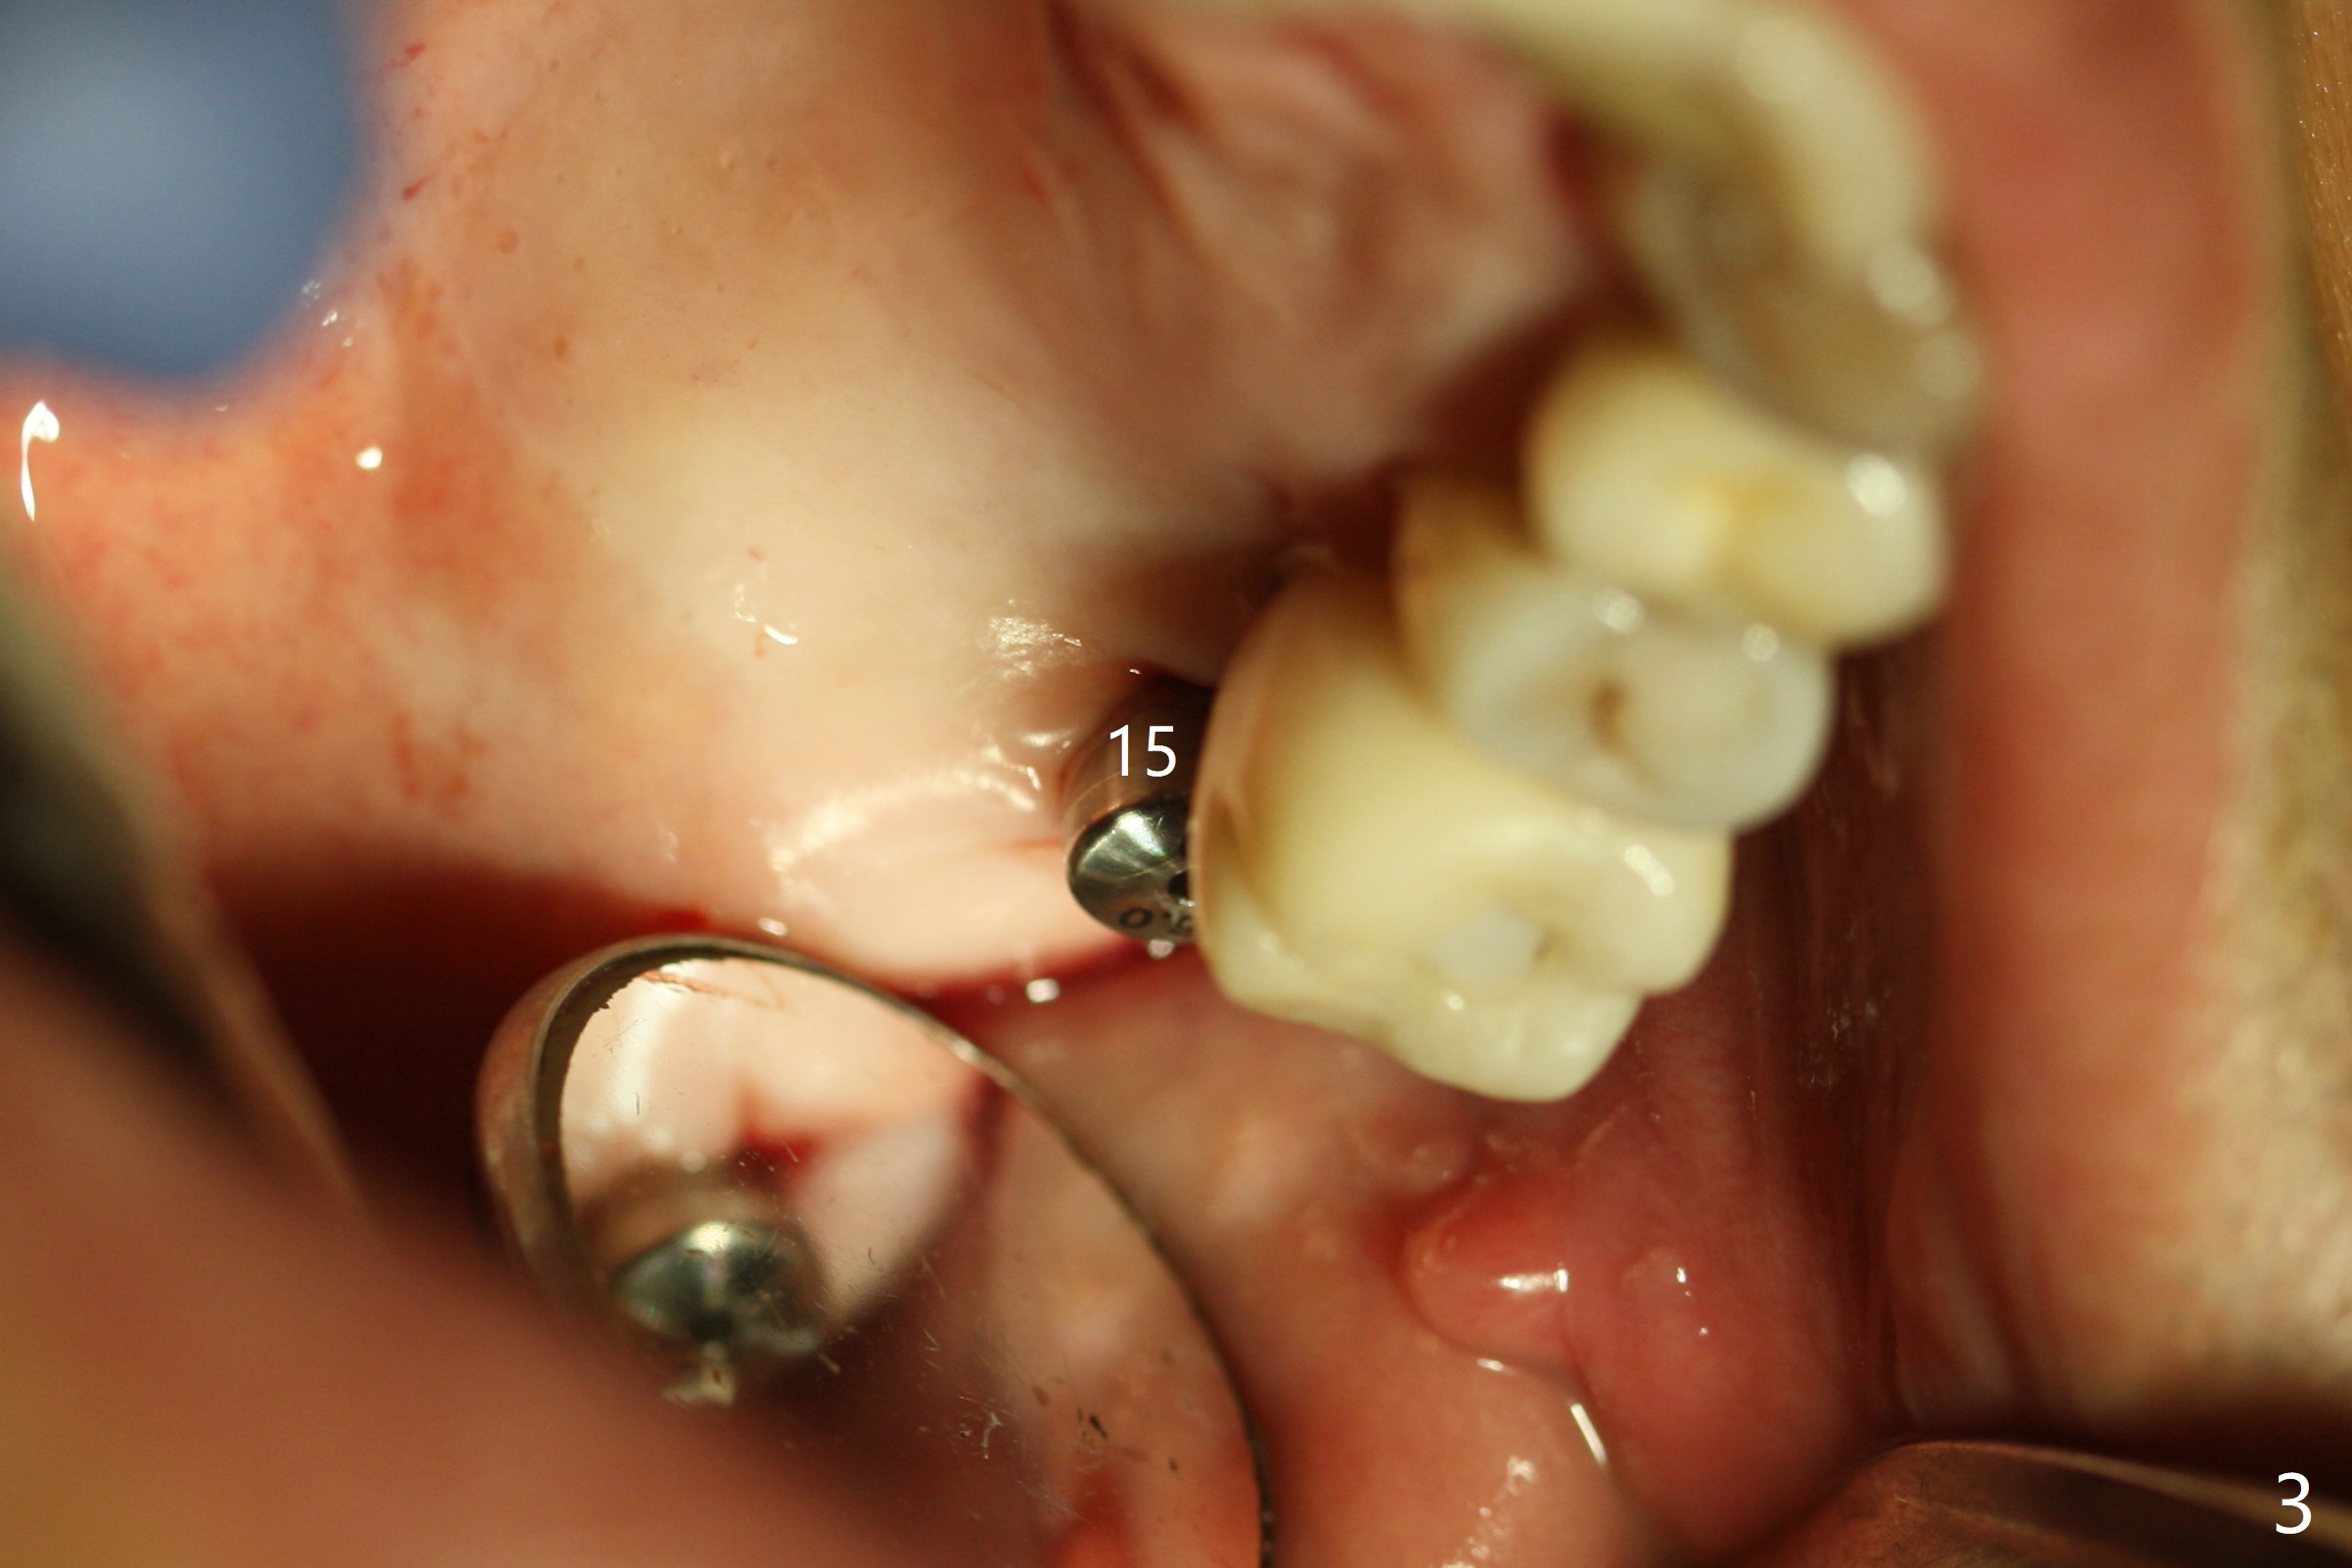

Today schedule is to extract the teeth #4 and 5 and place an implant at #5. When the latter is done, it appears that the implant at #15 should be placed at the same appointment (Fig.1). Once an abutment is placed at #5 (Fig.2 A, 5) for temporary crown (Fig.4 T) , the guide may be not seated again unless the crown is removed. Luckily the implant placement at #15 is quick and smooth with the guide (Fig.3,6). The implants seem to be covered by the bone 4 months postop (Fig.7,8). #15 abutment screw needs retightening because of long crown 1.5 months post cementation. Access hole is palatal. There is premature contact in lateral movement. The buccolingual occlusal table is large at #14 and 15. In fact there is more occlusal contact at #14 than #15 in centric occlusion. Tissue level implants should have been placed to reduce implant/abutment loosening. The incomplete abutment seating (Fig.5,7) is noted after retightening the loose cantilever FPD 1 year post cementation (Fig.9 <). After removal of the FPD, the abutment is reseated completely without interference of the proximal contacts (Fig.10).